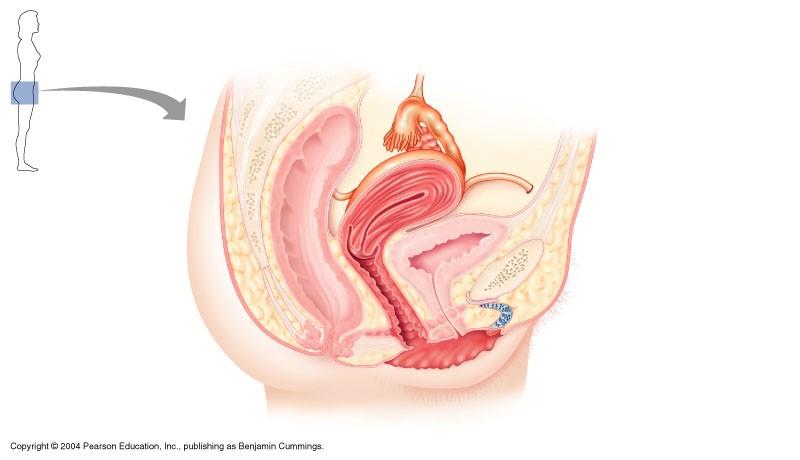

The indicated part of the female reproductive system is

cervix

the indicated part of female reproductive system is fundus of uterus

false

Female reproductive system

infundibulum

round ligament

cervix

vagina

uterosacral ligament

uterine tube